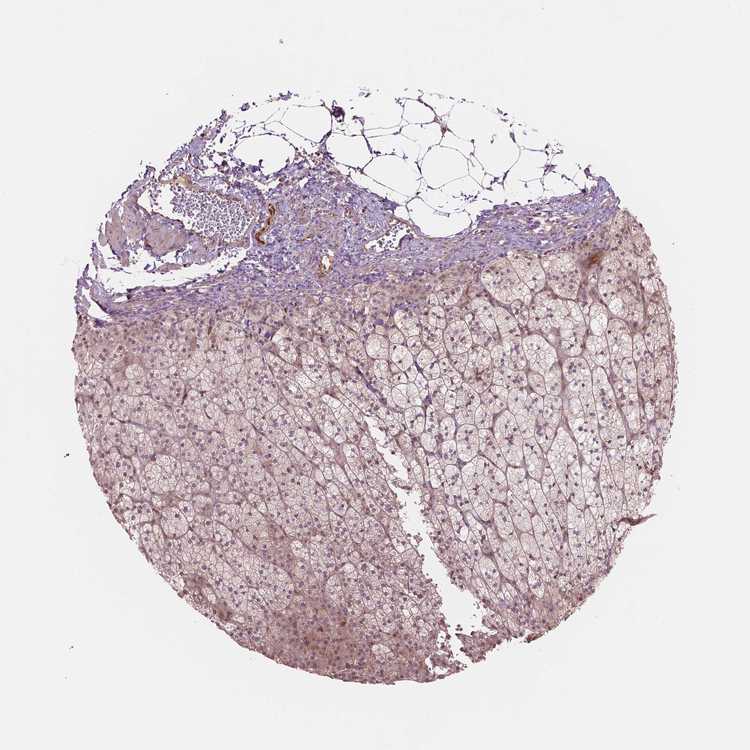

ADRENAL GLAND - Antibody stainingi

Antibody staining in the annotated cell types in the current human tissue is reported as not detected, low, medium, or high, based on conventional immunohistochemistry profiling in selected tissues. This score is based on the combination of the staining intensity and fraction of stained cells.

Each image is clickable and will lead to virtual microscopy that enables deeper exploration of all samples and also displays staining intensity scores, fraction scores and subcellular localization as well as patient and tissue information for each sample.

Antibody HPA071309

Glandular cells Low